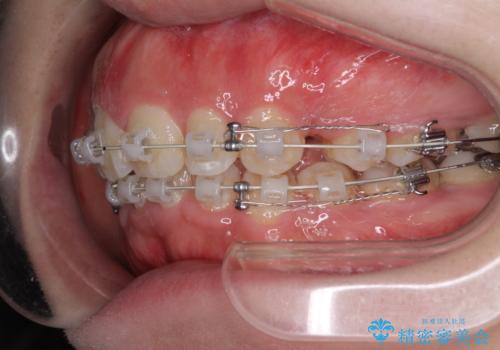

- 矯正装置

- 審美装置

- 治療期間

- 2年6ヶ月

- 治療回数

- 10-30回